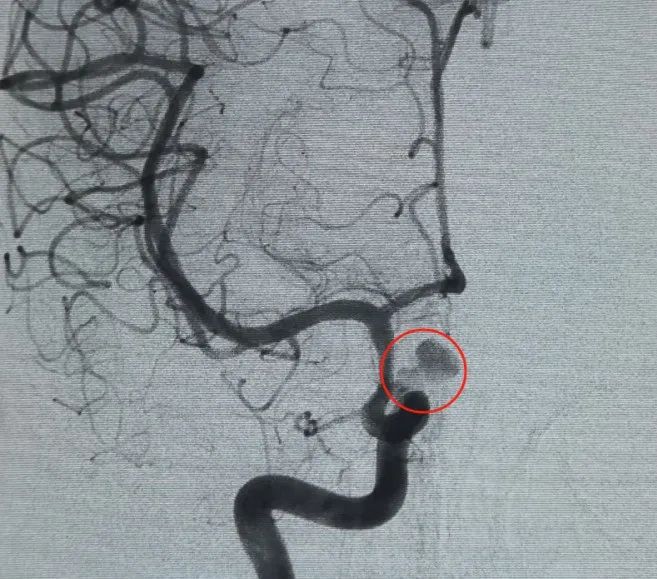

التشخيص: الجزء الأيسر من الشريان السباتي الداخلي C6 تمدد الأوعية الدموية في الشريان العيني

تم إنشاء الوصول إلى الأوعية الدموية عن طريق ثقب الشريان الفخذي ، ومكثف®تم نشر ملف 6 × 20 × 3D لأول مرة لتشكيل سلة ، وتحقيق تثبيت جداري ثابت وتوفير دعم آمن داخل التقاص. وأعقب ذلك إدخال بيدنزر®6 × 15 ملف ثلاثي الأبعاد لتعطيل تدفق الدم داخل كيس الابنة المفصص.

A periller®3 × 6.9 لفائف قابلة للتوسيع®ثم وضع ملف 3 × 2 قابل للتوسيع لإكمال انسداد الرقبة. بعد ذلك ، Nuva®تم تسليم وتحويل التدفق (، أونشرم) عبر الرقبة تمدد الأوعية الدموية. أكد التصوير الوعائي للمتابعة في كل من المنظرين الجانبي والخلفي تغطية ممتازة ، وتأويل جيد للجدار ، وشفافية واضحة ، مع ركود ملحوظ في التباين.